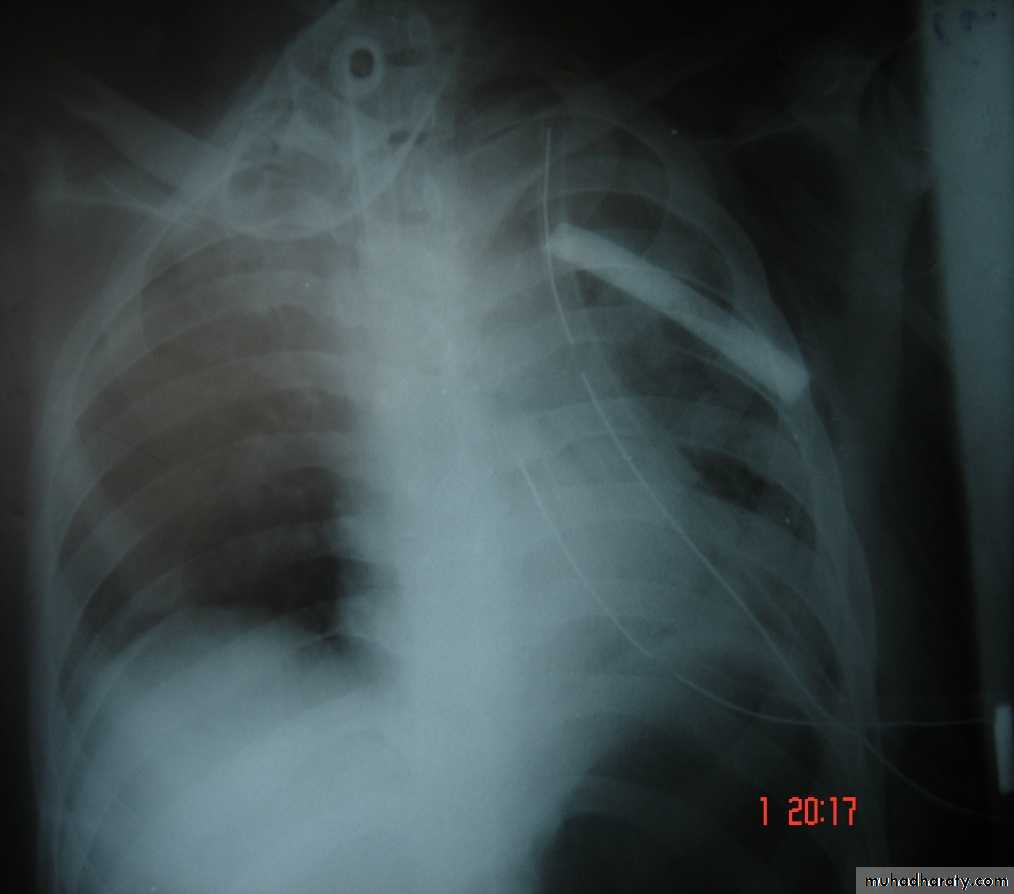

• 6-Great vessels injuriesInjuries to the thoracic aorta and its branches can occur mainly with deceleration injury . Most patients with ruptured aorta die immediately but in 10% of patients the per aortic tissues and pleura are able to maintain the intravascular pressure producing false aneurysms ,which can be diagnose by CT angiography and needs immediate surgery .

Traumatic aortic disruption is a time-sensitive injury requiring rapid and accurate diagnosis to prevent death.

Widen mediasinum

Descending aortic injuryEndo vascular stent control